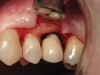

Figure 3  Clinical photograph of maxillary left lateral incisor implant restoration in a 60-year-old man. Implant had been restored 5 years earlier. The thick gingival tissue demonstrated redness and cyanotic color changes, swollen marginal contour, and loss of fibrous tone; bleeding and suppuration was noted on probing.

Figure 3

Figure 5  Excess cement noted below the crown margin resulting in peri-implant inflammation as shown in Figure 3. After facial and palatal flap elevation for direct visualization, excess cement was removed with curettes. Care was taken to avoid scratching the abutment surface. The site was irrigated with a 0.12% chlorhexadine-based oral rinse; flaps were replaced and closed with resorbable gut suture.

Figure 5